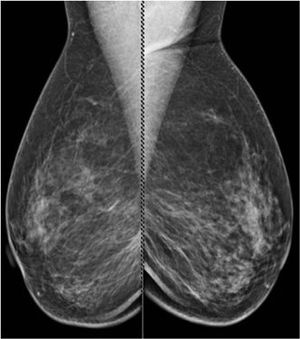

A 54-year-old patient presented for evaluation of spontaneous left breast discharge. The patient is status post-right mastectomy with TRAM reconstruction in 1999. The patient states she has noted left breast discharge for quite some time